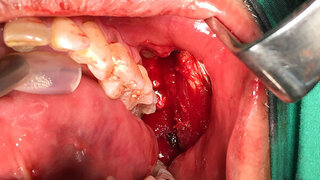

Weltnichtraucher-TagDer Zahnarztbesuch ist auch Krebsvorsorge Am 31. Mai ist Weltnichtraucher-Tag der WHO. Die Initiative proDente stellte dieses Jahr Leukoplakien in den Fokus und machte deutlich, warum der Zahnarztbesuch auch gleichzeitig Krebsvorsorge ist. 31.05.2022 Gesellschaft